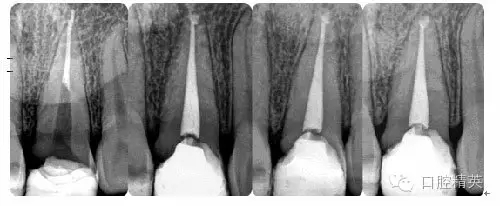

病例5:遺漏根管再治療

病例6:折斷器械取出